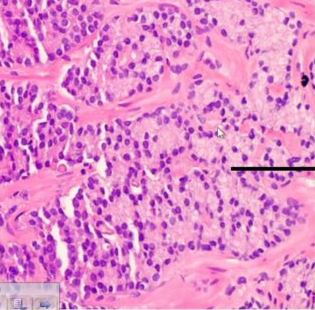

What Gleason Grade?

Grade 2